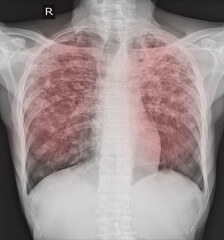

폐결절은 폐에 형성되는 작은 덩어리 또는 종양을 의미합니다. 이러한 결절은 폐의 X선이나 기타 영상 검사를 통해 발견될 수 있으며 다양한 원인에 의해 발생할 수 있습니다. 폐결절은 종종 미립자, 감염, 염증, 혹은 기타 조직의 비정상적인 성장으로 인해 형성될 수 있습니다.

흉부 X선 검사

폐결절은 보통 흉부 X선으로 처음 발견될 수 있습니다. X선은 폐결절의 크기와 일반적인 특징을 파악하는 데 도움이 될 수 있습니다. 그러나 X선은 폐결절의 세부적인 특성을 파악하기에는 제한적일 수 있습니다.